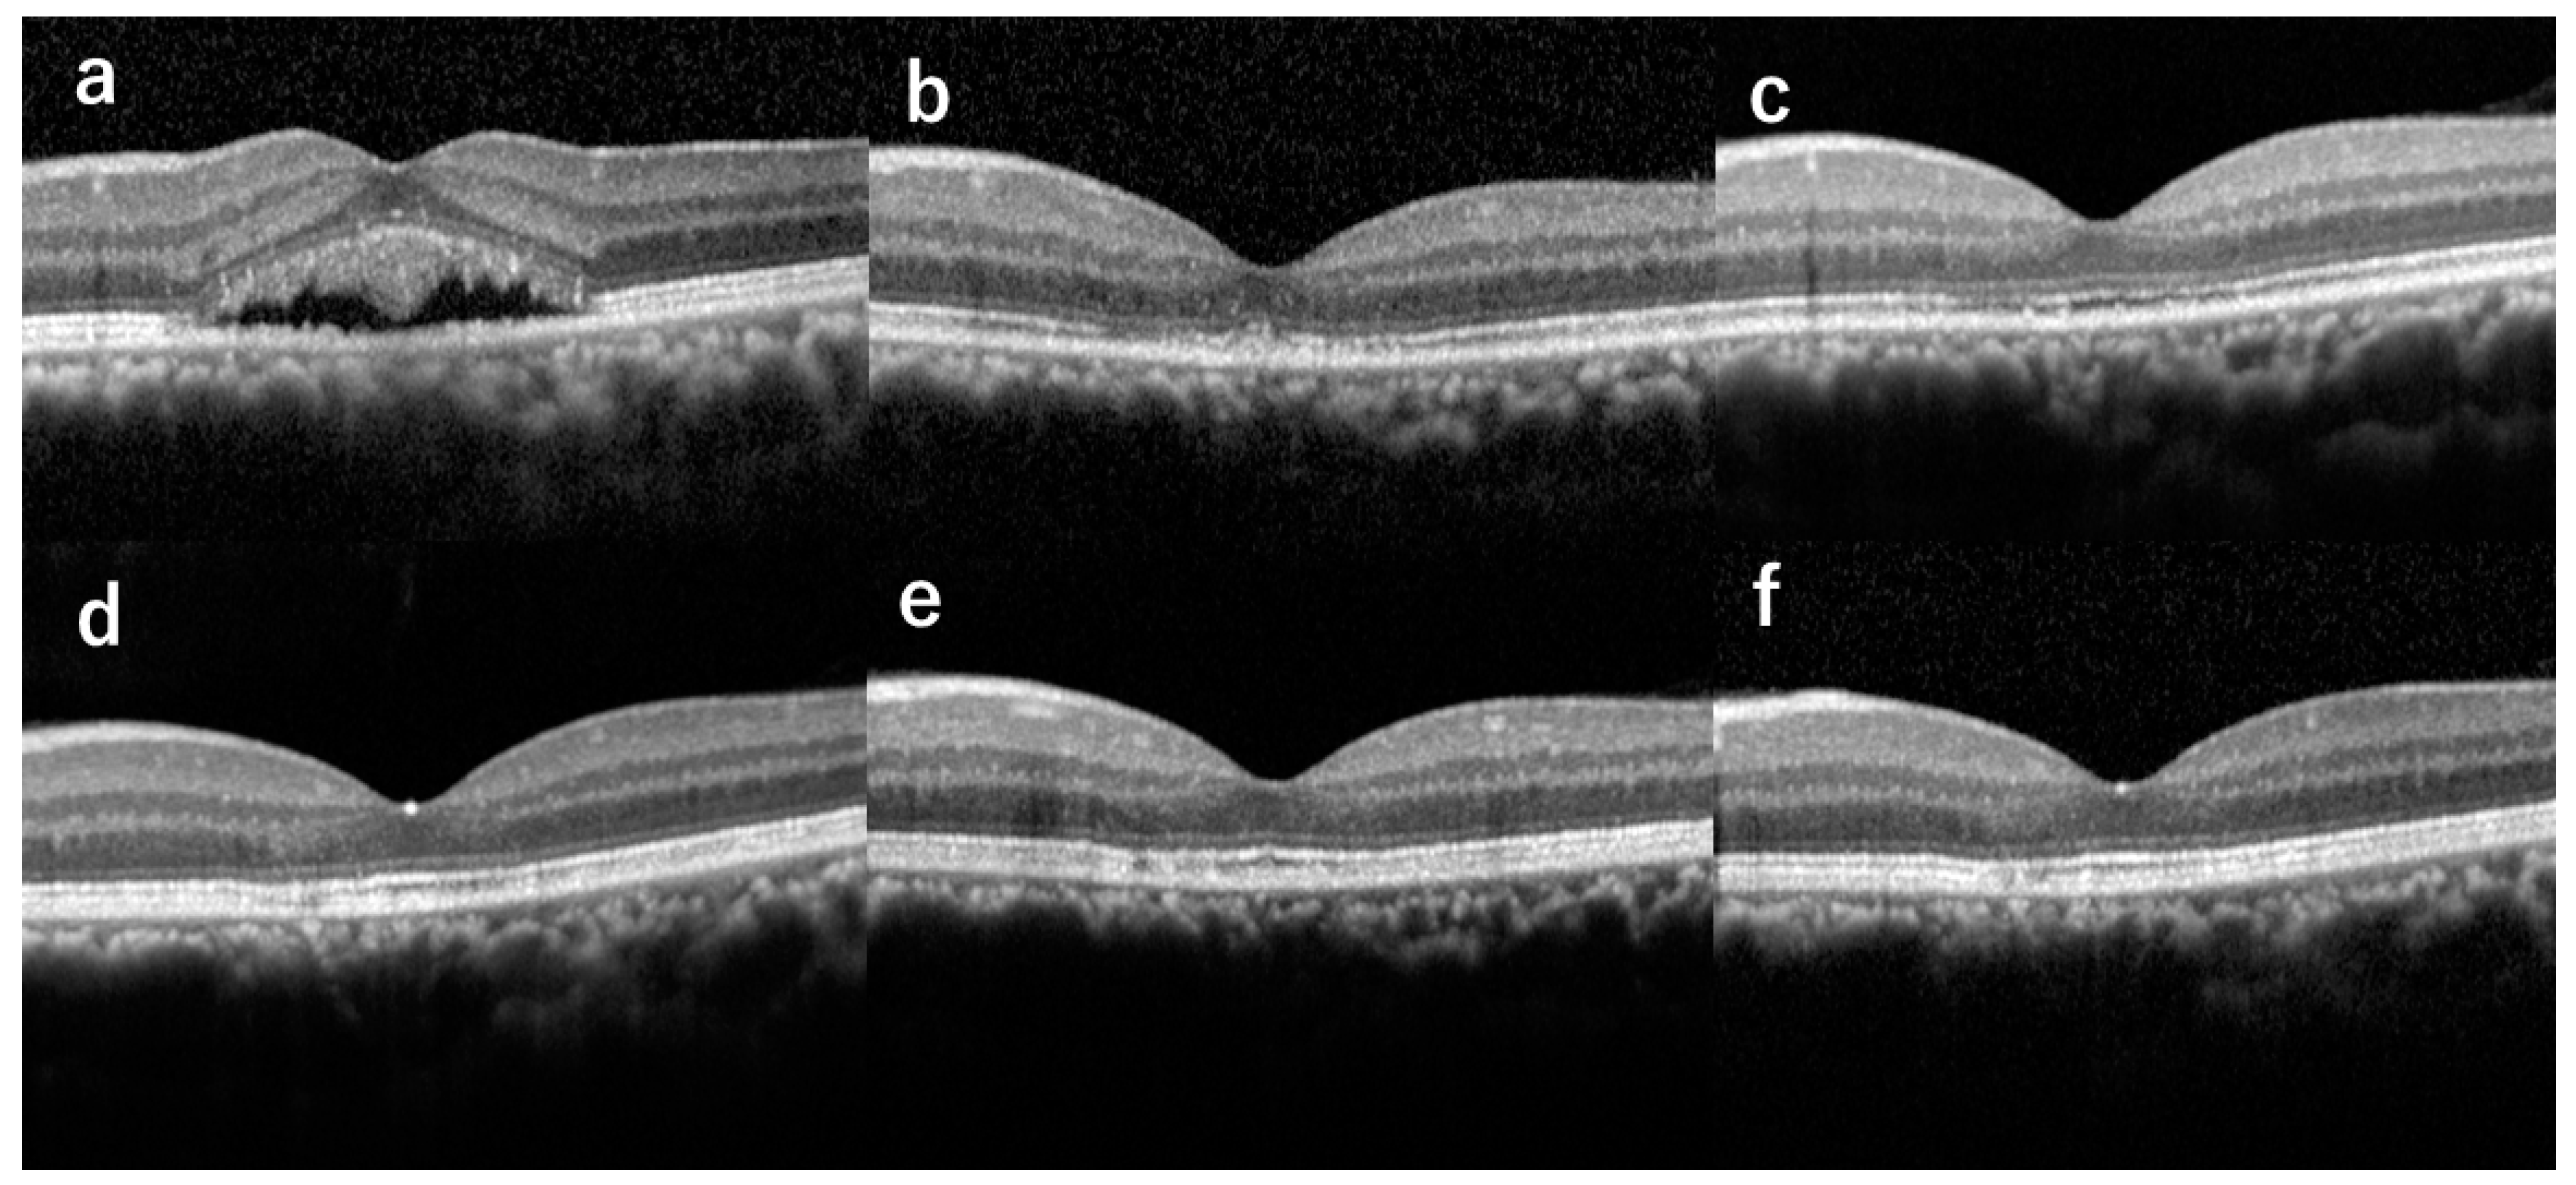

Ellipsoid zone and interdigitation zone were not detectable in all the eyes before hdPDT (Table 1 and Figure 1). Ellipsoid zone at the fovea was observed in 2 of 8 eyes at 1 month, in 7 of 8 eyes at 3 months, and in all 8 eyes from 6 months. The interdigitation zone was first detected at 9 months in 2 eyes, and continuous interdigitation zone was seen at 12 months in 6 eyes (Figure 2).

Figure 2.

Optical coherence tomography images of the left eye of a 41-year-old male (Case 1) with chronic central serous chorioretinopathy showing serial changes of the ellipsoid zone (EZ) and interdigitation zone (IZ), from before half-dose photodynamic therapy (hdPDT) to complete recovery of the two zones after hdPDT. In this case, the serous retinal detachment was completely absorbed at 1 month after hdPDT. (a) Before hdPDT, EZ and IZ at the fovea were both absent. (b) At 1 month after hdPDT, EZ and IZ were both absent. (c) At 3 months, EZ was continuous and IZ was absent. (d) At 6 months, EZ was continuous and IZ was fragmented. (e) At 9 months, EZ was continuous and IZ was fragmented. (f) At 12 months, EZ and IZ were both continuous.